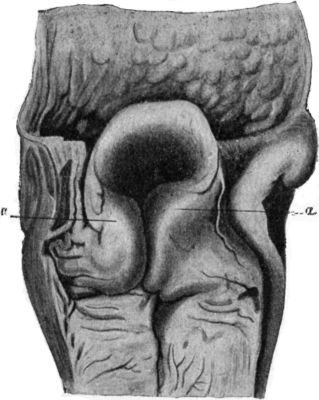

| 80. | Section of Knee-joint showing Extent of Synovial Cavity | 156 |

| 123. | Lower End of Femur from an Advanced Case of Tuberculous Arthritis of the Knee | 231 |

| 124. | Advanced Tuberculous Disease of Knee, with Backward Displacement of Tibia | 233 |